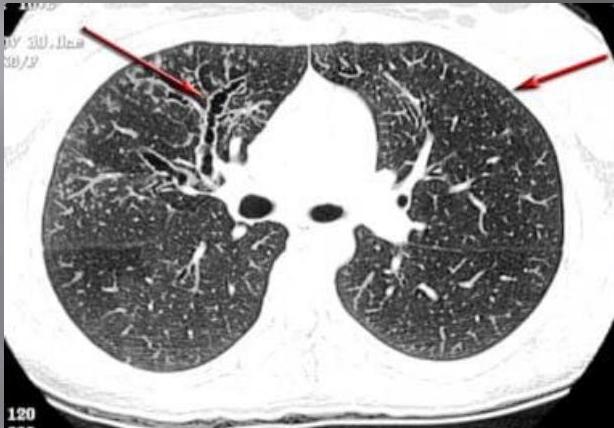

Chest radiograph findings:

- Usually normal

- May show hyperinflation

- May reveal pneumomediastinum

Additional imaging:

- High-resolution computed tomography (HRCT) is necessary to clarify any abnormalities noted on chest radiographs